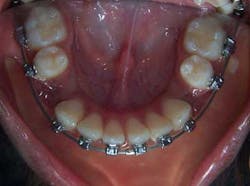

Therefore, the treatment plan for Rachael was based mainly on her facial appearance as opposed to any tooth irregularity. Despite the fact that there was no crowding, extraction of four bicuspids was still indicated, with the goal of creating space for retraction of the incisors.

Uprighting the incisors resulted in better facial balance, elimination of mentalis strain and retraction of the protruded lower lip.